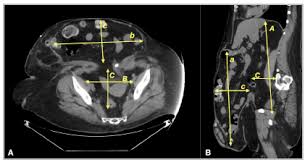

Ct Scan Abdomen Showing Hernia With Divarication Arrows Shows Download Scientific Diagram